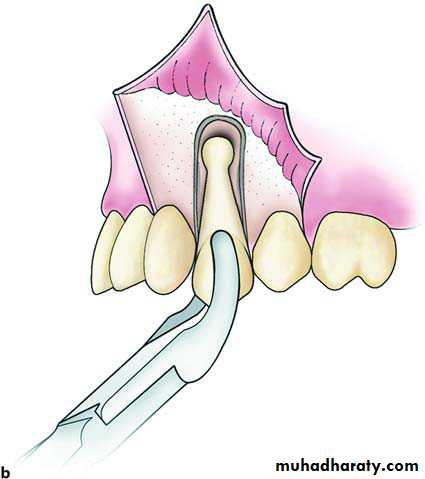

If the tooth is accessible after flap reflection we can do one of the following :

1/ Reset the forceps under direct vision2/ Using straight elevator a